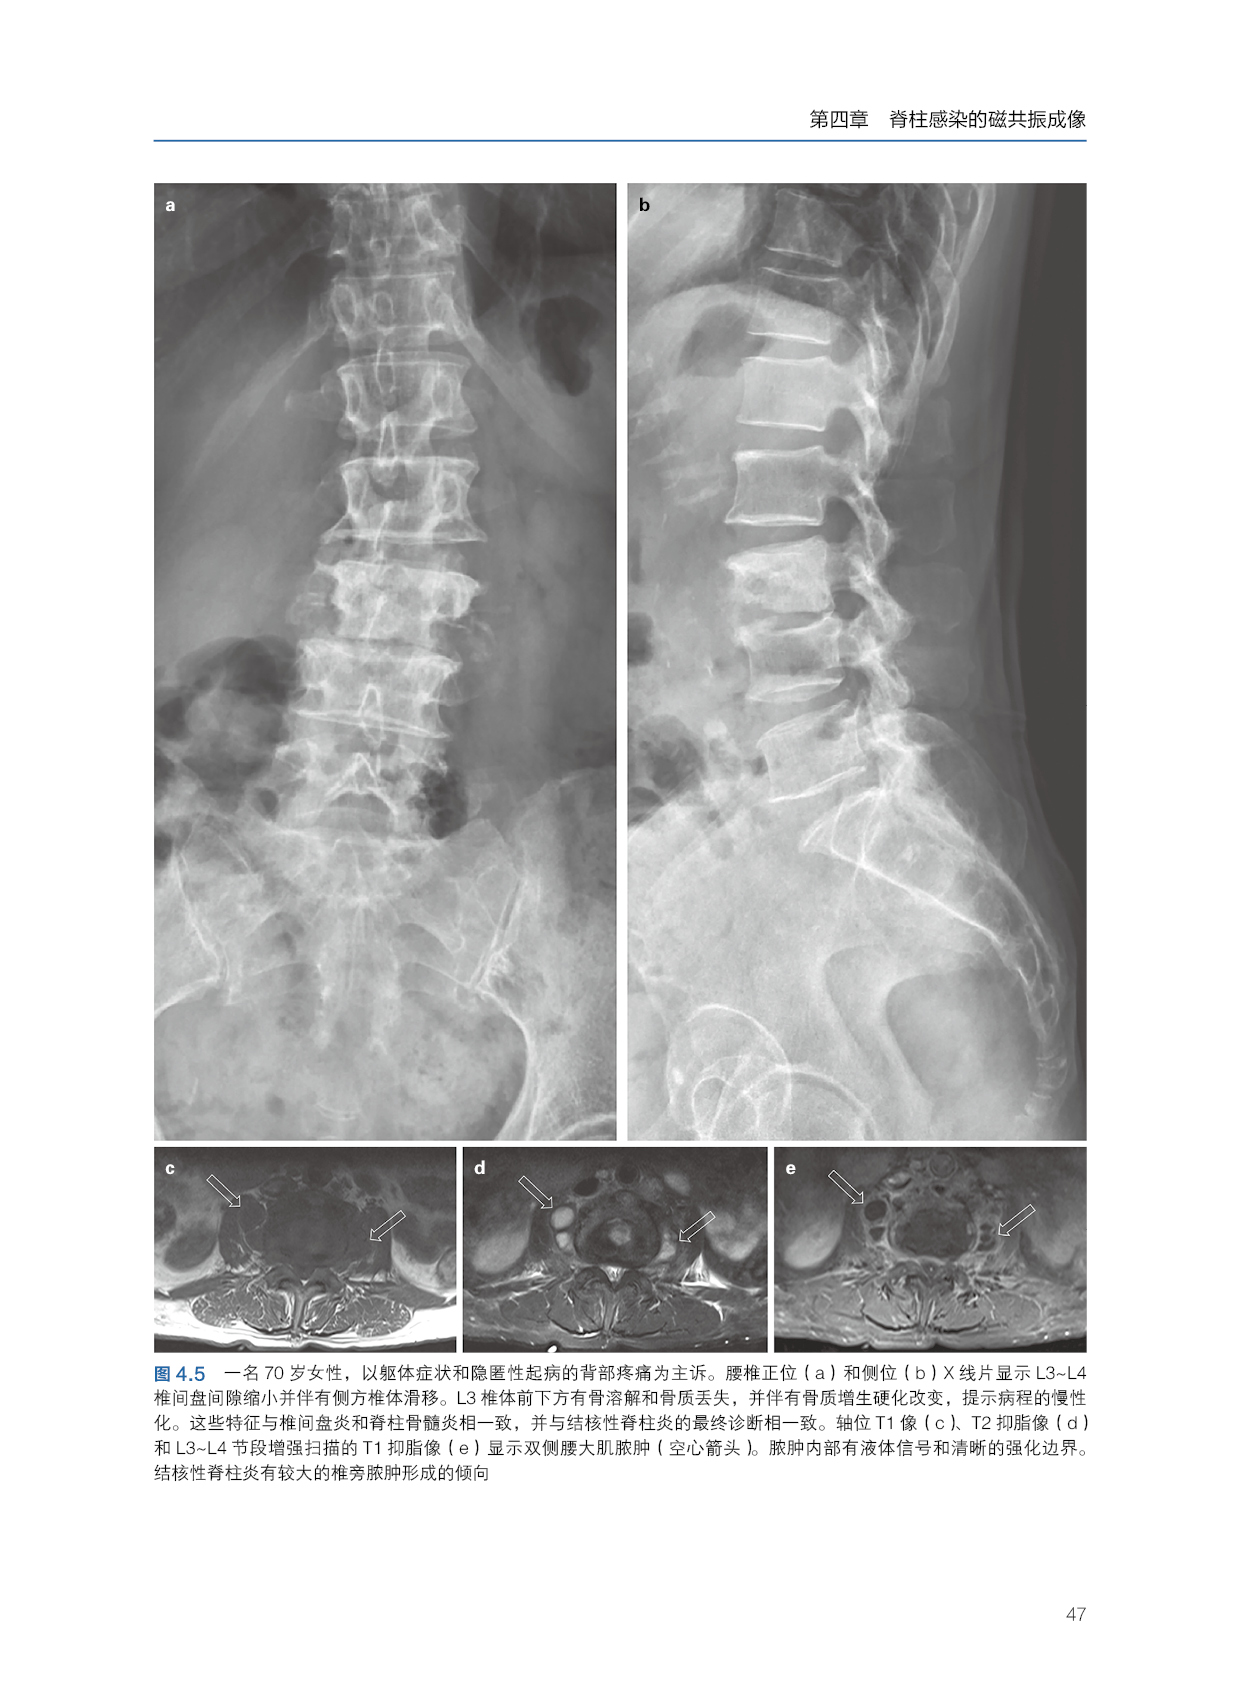

本书主要包含脊柱感染的X线摄片和计算机断层扫描、脊柱感染的经皮穿刺活检、化脓性硬膜外脓肿的影像学、影像学分析(文字分析)、影像学示意图、影像学真实临床影像图片。文字部分的讲解深入浅出,详细且非常便于理解。示意图可以更好地让读者明白和掌握,而临床图片更是将理论与临床实践紧密结合起来。